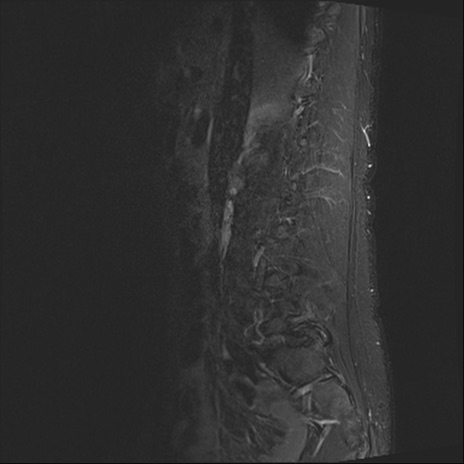

【整形】TIPS症例4 腰椎MRI STIR(矢状断像)

腰椎MRI